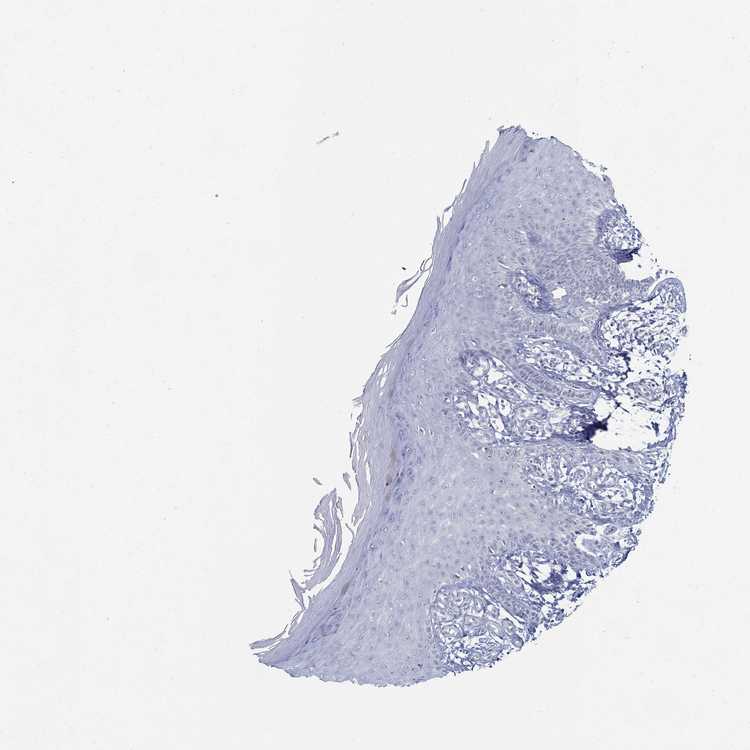

SKIN 1 - Antibody stainingi

Antibody staining in the annotated cell types in the current human tissue is reported as not detected, low, medium, or high, based on conventional immunohistochemistry profiling in selected tissues. This score is based on the combination of the staining intensity and fraction of stained cells.

Each image is clickable and will lead to virtual microscopy that enables deeper exploration of all samples and also displays staining intensity scores, fraction scores and subcellular localization as well as patient and tissue information for each sample.

Antibody HPA076515

Langerhans Not detected

Fibroblasts Not detected

Keratinocytes Not detected

Melanocytes Not detected